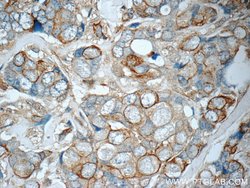

This antibody is specifically against KRT7.

Cytokeratin 7 blocks interferon-dependent interphase and stimulates DNA synthesis in cells. Involved in the translational regulation of the human papillomavirus type 16 E7 mRNA (HPV16 E7).Specifications

| Immunocytochemistry, Immunofluorescence, Immunohistochemistry (Paraffin), Immunoprecipitation, Western Blot | |